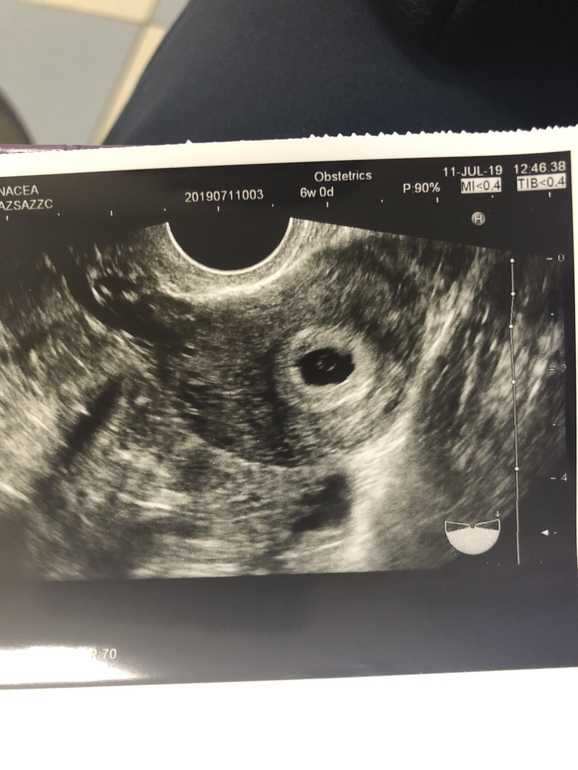

Вот мое узи ровно в 6 недель

14.10.2019